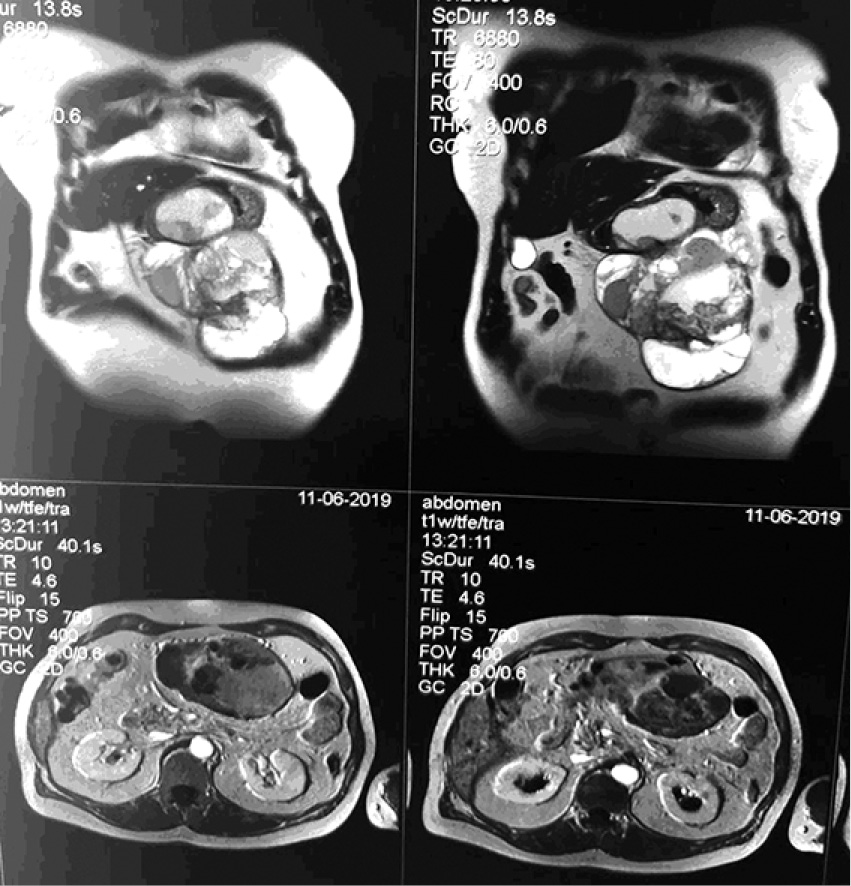

- МРТ с контрастированием от 11.06.2019 г. Заключение: Объёмное образование брюшной полости слева, кистозно-солидной структуры со сдавлением желудка (tumor). Множественные кисты обеих долей печени. Конкремент желчного пузыря. Увеличенные забрюшинные лимфатические узлы (рис. 1–4).

Рис. 1. Увеличенные забрюшинные лимфатические узлы

Рис. 2. Увеличенные забрюшинные лимфатические узлы

Рис. 3. Увеличенные забрюшинные лимфатические узлы

Рис. 4. Увеличенные забрюшинные лимфатические узлы